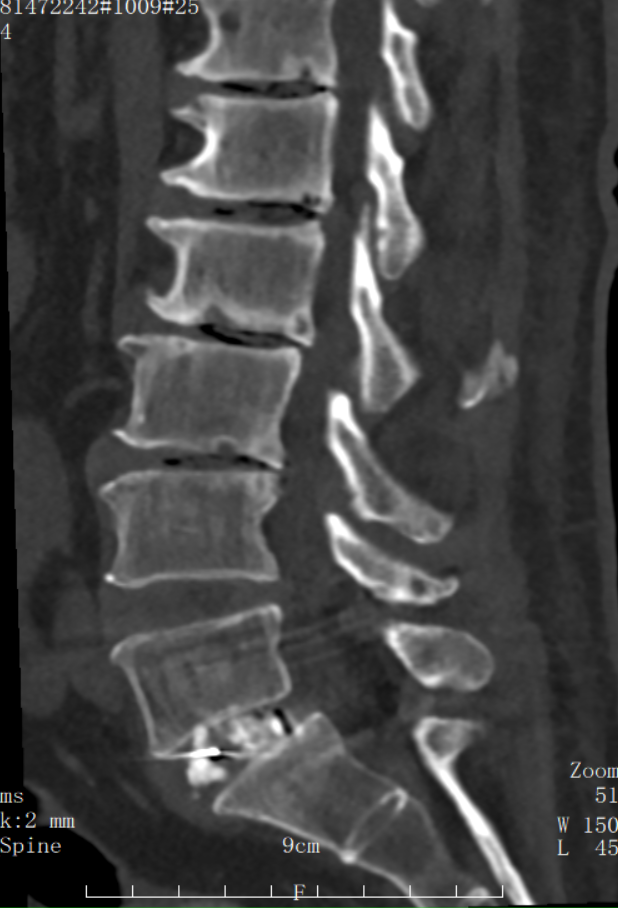

▲術后CT檢查

有效融合:在解除壓迫的同時,植入融合器并輔以內固定,進行滑脫復位,重建了腰椎的穩定性。

恢復迅速:由于對腰部肌肉和軟組織損傷極小,患者術后第二天即可在支具保護下下床活動,大大降低了臥床并發癥的風險,縮短了住院和康復時間。